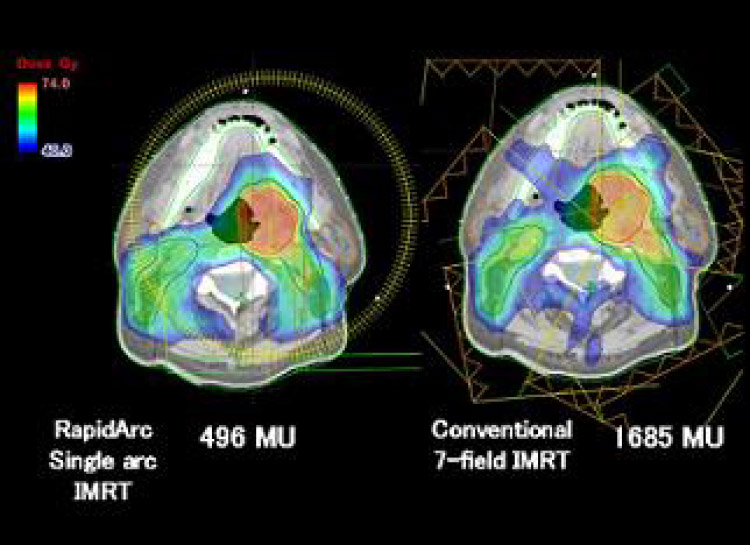

治療計画コンピューターも最新バージョンに更新され、頭部のみならず全⾝の腫瘍に対し⾼精度放射線治療(定位放射線治療、強度変調放射線治療︓IMRT(回転IMRT RapidArcを含む)、画像誘導放射線治療︓IGRT)が可能となります。

治療計画コンピューターも最新バージョンに更新され、頭部のみならず全⾝の腫瘍に対し⾼精度放射線治療(定位放射線治療、強度変調放射線治療︓IMRT(回転IMRT RapidArcを含む)、画像誘導放射線治療︓IGRT)が可能となります。

回転IMRT(Rapid Arc)計画も可能

中咽頭癌例 左右の唾液腺を守るIMRT

通常IMRTよりさらに分布が改善

中咽頭癌例 左右の唾液腺を守るIMRT

通常IMRTよりさらに分布が改善